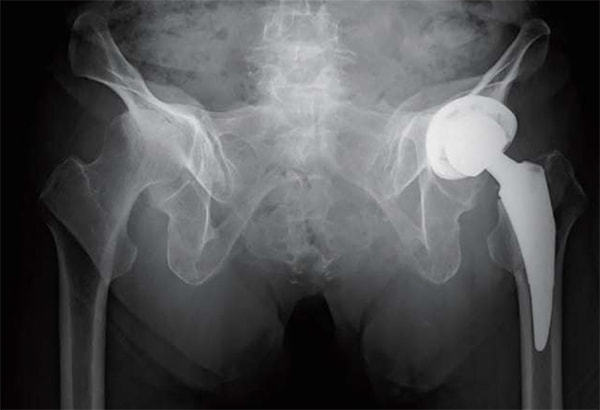

人工股関節置換術において従来の後側方アプローチ(Posteo Lateral Approach)に加えて、2015年より前方アプローチ(Direct Anterior Approach)を積極的に取り入れて参りました。

これは脱臼率の低下に加えて、筋間アプローチによる低侵襲手術を提供するという目的によるものです。これにより在院日数は低下し、術後の姿位制限を撤廃したことで、前述のスポーツ復帰率の向上を図ることができるようになりました。また、高齢化に伴い生じる脊椎変形、脊椎固定術後の矢状断アライメントの変化に対応できるよう、CUPは透視を用いて動的に評価しながら至適位置に設置することで良好なstabilityが得られています。

仰臥位股関節Xp

立位股関節Xp

立位で骨盤後傾を伴う

術後 立位股関節Xp